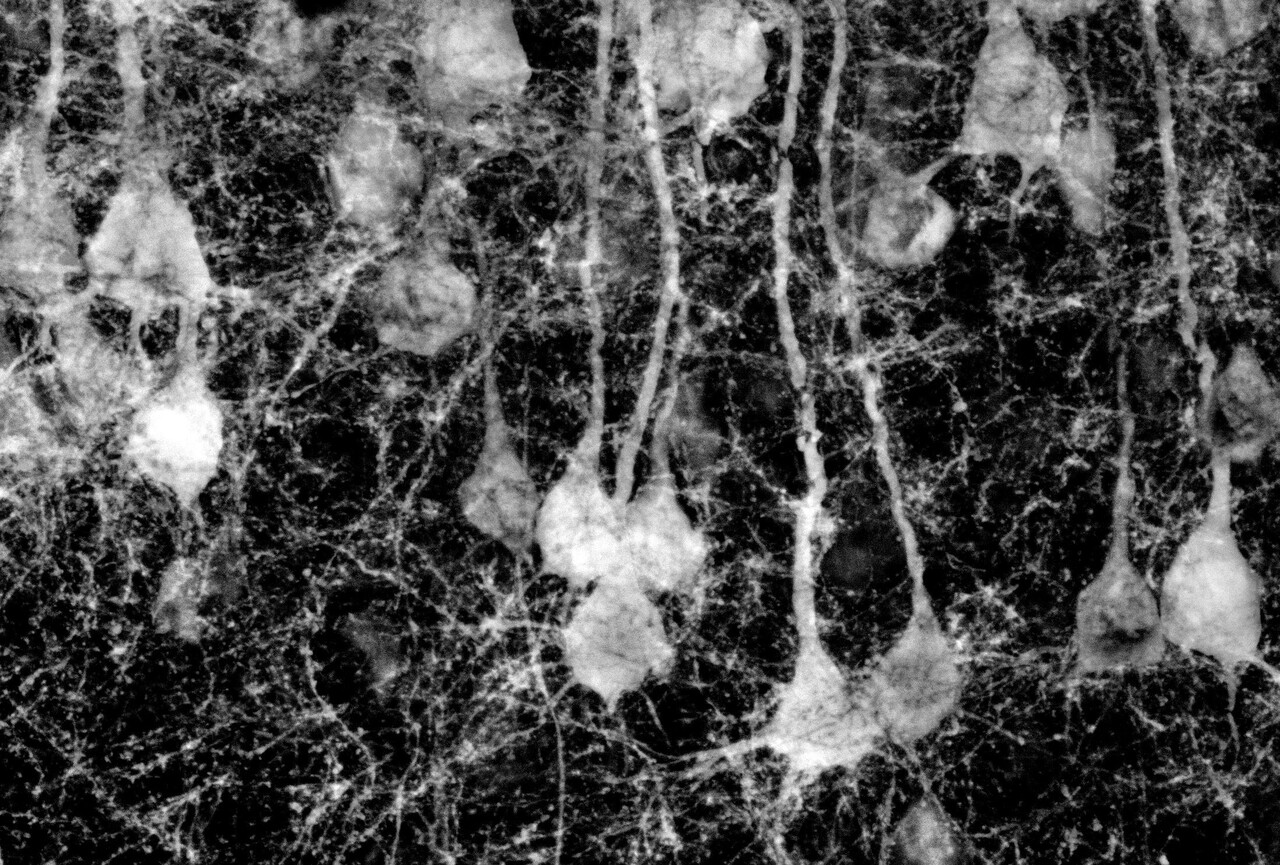

To understand why social behavior was altered, we explored connections with the LCN to the prefrontal cortex. We analyzed multiple regions of the prefrontal cortex, but found only specific changes to neural firing and structure within the anterior cingulate cortex (ACC). Interestingly, a subtle developmental disruption to the LCN was enough to reorganize activity across three major brain regions known for motivation, reinforcement learning, and cognitive control: the ventral tegmental area (VTA), nucleus accumbens (NA), and anterior cingulate cortex (ACC). These are not places traditionally associated with cerebellar function, yet activity shifted in a circuit-level way that traced back to the cerebellum. Not only were these changes in LCN-VTA-NA-ACC connections functional, but we observed structural remodeling of neurons in the ACC suggesting that the cerebellum shapes these cortical circuits in development.